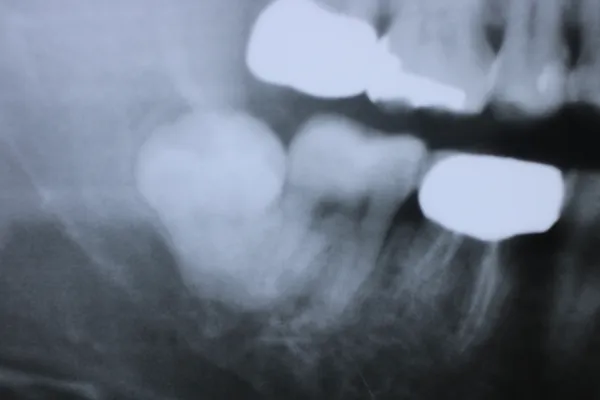

6入れ歯にしないブリッジ治療【ケース3】

このケースの患者さんは上の歯の歯槽膿漏が心配で来院されました。上の歯は11本残っており、下の写真の緑色に囲われた歯を1本抜歯して、計10本の歯を使って端から端まで繋げる治療を行いました。H22.5月に治療が始まり、H23.1月に完成しました。

H22.5のレントゲン

H31.2月には下の写真の青色に囲われた歯が根の先の病気でダメになり抜歯をすることになりましたが、歯の見えている部分はそのままで根だけを切って抜歯しました。そのため1本歯が少なくなり、9本で端から端まで繋がっています。

H31.2のレントゲン

下のレントゲン写真はR3.12月に撮影した写真ですが、赤丸の歯槽膿漏の歯は1枚目のH22.5月の頃からほとんど変化しておらず、13年経っても大丈夫です。全部の歯が繋がっていて、1本1本の歯の動きがないため、長く維持できています。

R3.12のレントゲン